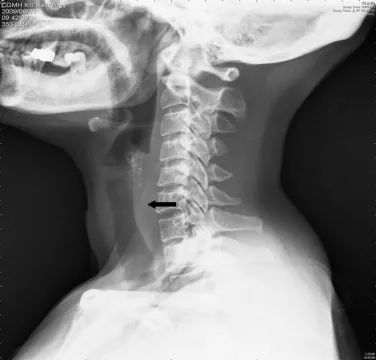

一名25岁的囚犯由于腹部疼痛被警卫带到了医院,X光检查发现了他体内的剃须刀片。更神奇的是,被发现时刀片已经转移到了他的阑尾,这种情况极其罕见。